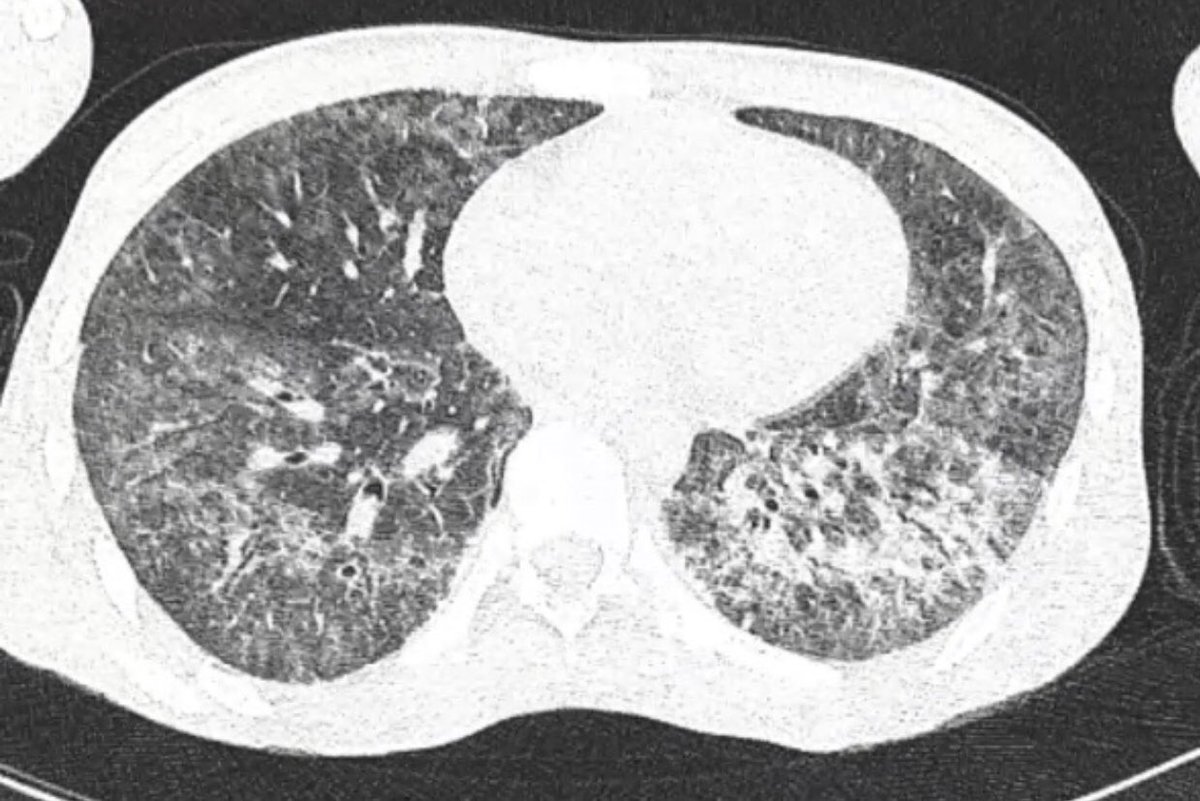

Jigsaw puzzling in the ICU: diagnosing invasive pulmonary aspergillosis.

@drjordirello@PneumoINSPIRE@VVIZV1#fungus#aspergillus#ICU#aspergillosis@JMellinghoff@marta_bork@WendyChaboyer@RKleinpell@BronaghBelfast@drbencb https://www.ncbi.nlm.nih.gov/pubmed/31361683 pic.twitter.com/lAynu8h3E6